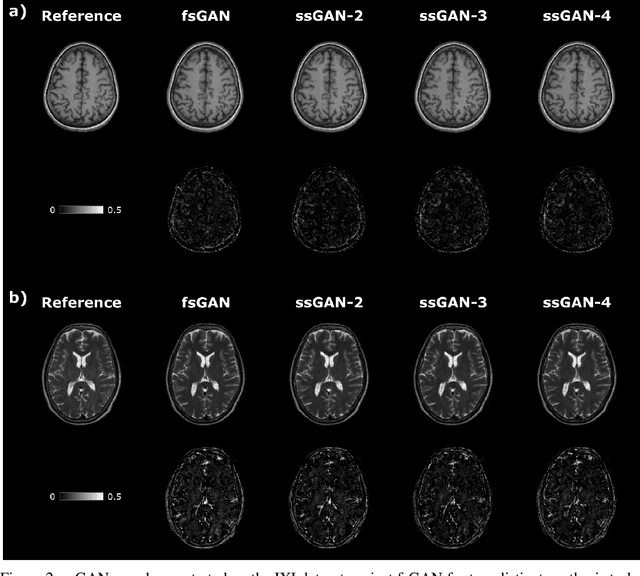

Abstract:This study proposes a novel semi-supervised learning framework for mutually accelerated multi-contrast MRI synthesis that recovers high-quality images without demanding large training sets of costly fully-sampled source or ground-truth target images. The proposed method presents a selective loss function expressed only on a subset of the acquired k-space coefficients and further leverages randomized sampling patterns across training subjects to effectively learn relationships among acquired and nonacquired k-space coefficients at all locations. Comprehensive experiments performed on multi-contrast brain images clearly demonstrate that the proposed method maintains equivalent performance to the gold-standard method based on fully-supervised training while alleviating undesirable reliance of the current synthesis methods on large-scale fully-sampled MRI acquisitions.